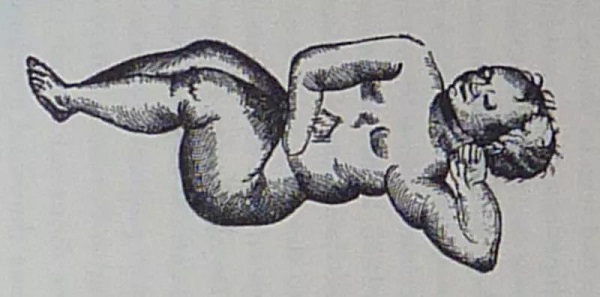

外科医生纪录的桑斯胎儿的形象

这里面竟是一个蜷缩着的女胎,连头发纹理、牙齿以及未闭合的囟门都清晰可见。

她的头部略微朝左倾斜,并由左臂支撑。

其右臂则向肚脐位置延伸,半截手臂末入腹中。